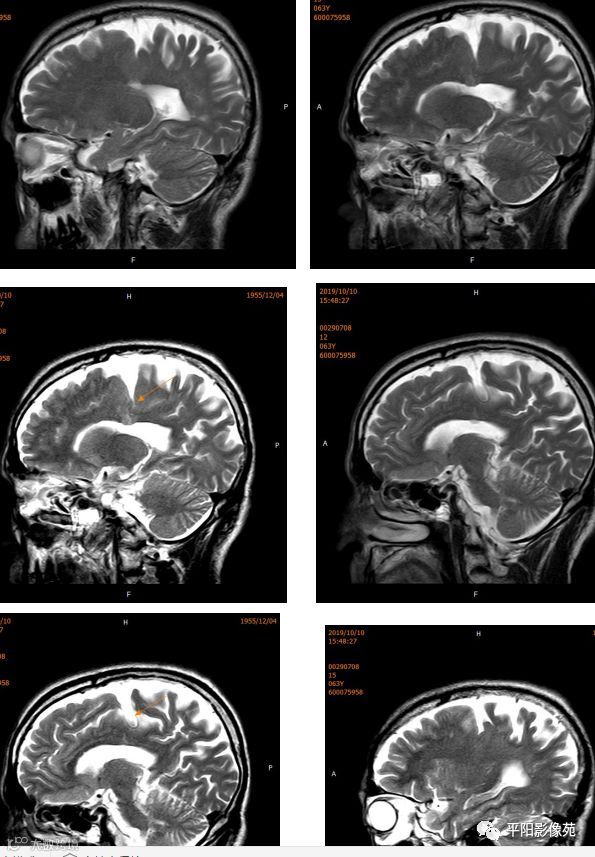

右侧额叶中央前回局部脑裂增宽,并向内延伸,周围衬以等灰质信号,呈稍长T1稍长T2信号,病灶自软脑膜向内延伸,与室管膜相连。